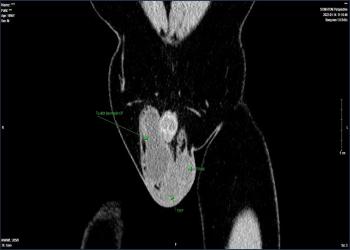

Chuyên ngành của TS.BS Nguyễn Đình Liên là khám, chẩn đoán và phẫu thuật các bệnh lý thận, tiết niệu, nam học.

Chữa tinh hoàn ẩn, viêm tinh hoàn, rối loạn cương dương, sỏi thận, bệnh yếu sinh lý…

Phẫu thuật sỏi thận, mổ Nội soi điều trị thoát vị bẹn, tinh hoàn di động, tràn dịch màng tinh hoàn…